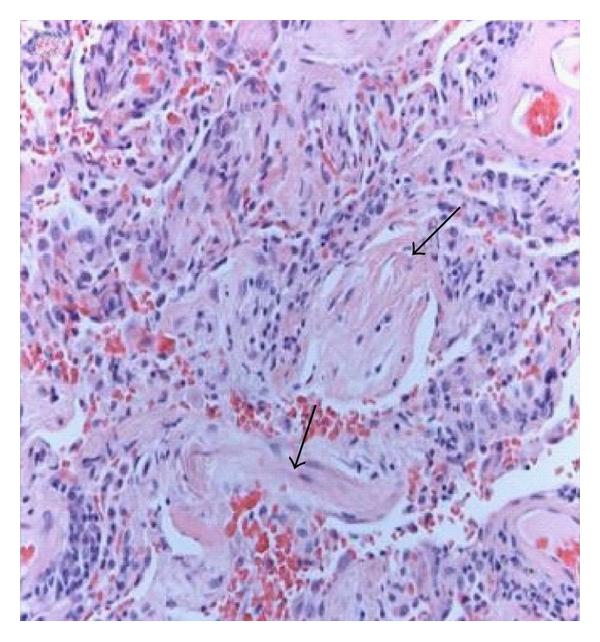

AIP was firstly described by Hamman and Rich in 1935 [22]. For many decades the patients in this first paper were assumed to have been suffering from UIP/IPF, in fact, it was 1990 when these patients were shown to truly suffer from AIP [23]. Clinically AIP presents as a rapid development of respiratory failure in a previously healthy person [24, 25]. Both clinically and radiologically, it usually displays the features of ARDS, but in contrast to ARDS, no specific cause as an aetiology can be found, therefore it could be considered as “idiopathic ARDS” [26, 27] (Figure 1(a)–1(d)). The histological pattern of AIP is typically DAD with hyaline membranes, edema, and interstitial acute inflammation [28]. In the organizing phase of DAD (approximately 5–10 days after injury), alveolar septal thickening with loose organizing fibrosis, type II pneumocyte hyperplasia, and patchy or diffuse airspace organization can be found (Figure 1(c)). The prognosis of AIP is dismal and the mortality high. It has been suggested that by adopting an aggressive diagnostic approach, that is, mechanical ventilation with a lung-protective strategy, and the early institution of immunosuppressive therapy it may be possible to improve the clinical outcome of AIP [29–31]. Controlled prospective studies on the treatment of AIP are not available, not surprising since AIP is so uncommon and it is generally a very acute lung manifestation displaying some overlapping features with ARDS.

(c)